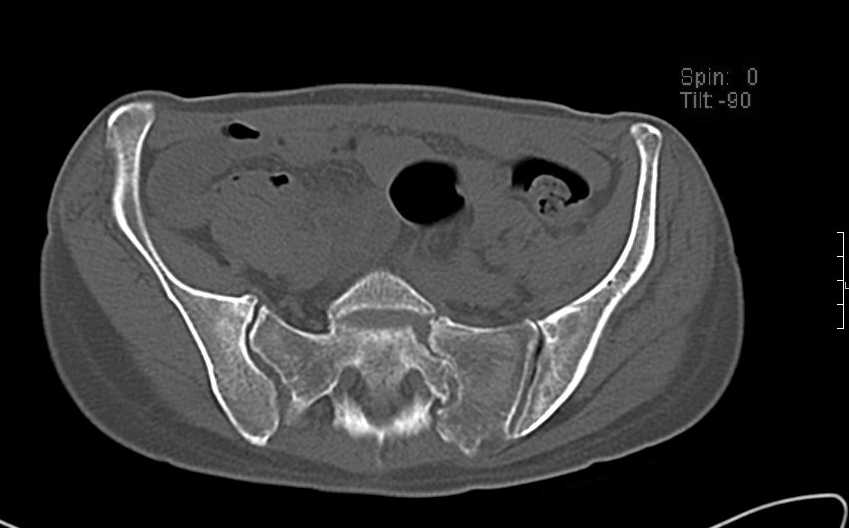

Больная 43 года (промышленный альпинист), 28.07.08 в результате падения с 5 этажа получила политравму: Перелом свода и основания черепа. Вертикально-нестабильное повреждение таза, осложнённое разрывом мочевого пузыря. Чрезвертельный перелом левого бедра. Перелом правой таранной кости, переломовывих правой кубовидной кости. Тупая травма живота, разрыв печени, ушиб почек. Забрюшинная гематома. В день травмы - лапаротомия, ушивание ран печени. Разрыв мочевого пузыря не диагностирован. Течение болезни осложнилось развитием мочевого затёка и обширной пред- и забрюшинной флегмоны, сформировался свищ мочевого пузыря. 19.8.2008 вскрытие, дренировние флегмоны, ревизия мочевого пузыря, обтурация мочевого свища (свищ закрылся в октябре), 1.10.2008 некрэктомия, пластика по Шеде-Лидскому правой кубовидной кости. По результатам КТ диагностирован рак правой почки (диагностическая находка), 8.10.2008 нефрэктомия справа. Переломы велись консервативно. Имеется вертикальное смещение левой половины таза с выраженным отведением крыла (клинически подвижности нет), несросшийся низкий двухколонный перелом левой вертлужной впадины с потерей конгруэнтности, укорочение около5 см, застарелый разрыв лонного сочленения, неправильно сросшиеся переломы обеих ветвей правой лонной кости с укорочением, патологическая подвижность лоно-седалищного фрагмента слева. Правая нижняя конечность неопорна, несмотря на то, что лежа прямую ногу поднимает, ходит на левой ноге (ортопедическая обувь) с костылями, справа тазобедренный ортез. Седалищные нервы работают.Урологи отпустили больную на 6 мес.

с большей вероятностью пациентка придет к эндопротезированию тазобедренного сустава, поэтому необходимо создать надежную "опору" сзади и подготовить бедро к имплантации любой классической ножки.ИМО бедренной кости GN, АНФ на таз,по необходимости остеотомия крестца, восстановление конфигурации задних отделов и устранение вертикального смещения половины таза. дождаться сращения крестца и бедренной кости. второй этап эндопротезирование: ножка цвай-мюллер или спаторно,ацетабулярно онкологическое антипротрузионное кольцо левое либо ацетабулярный компонент по индивидуальным параметрам для протезирования после резекции лонной седалищной костей и вертлужной впадины при онкопатологии. в кольцо пару трения металл\металл с цементной чашкой IMPLANTCAST, т.к. пациентка молодая.лонные кости можно оставить в покое, какой никакой рубец есть. с уважением Сергей.